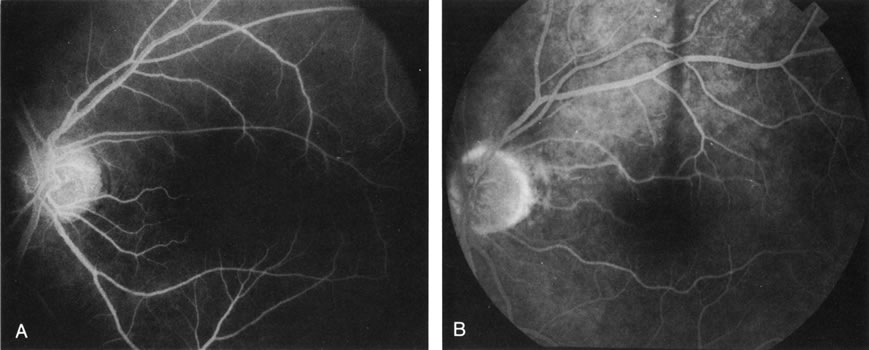

DIAGNOSIS Age-related macular degeneration (AMD) may be divided into two types. Nonexudative (“dry”) AMD has several morphologic forms, including “hard” discrete drusen, shallow retinal pigment epithelial detachments associated with thickened Bruch's membrane (“soft” drusen), and geographic atrophy (GA) of the retinal pigment epithelium (RPE).3 On FA the area of GA appears hyperfluorescent for window defect from the early frames of the angiogram, with late staining of the underlying sclera (Fig. 1). However, these pathologic changes can usually be assessed by clinical examination, and FA is generally not necessary to diagnose nonexudative AMD. An exception is cuticular drusen, which may appear clinically as a subtle disturbance of the RPE; FA reveals multitudes of small, discrete drusen described as “stars in the sky” (Fig. 2). The second type of AMD, which is associated with soft drusen, is known as exudative (“wet”) AMD. It is due to a choroidal neovascular membrane that has incompetent vessels resulting in detachments of the RPE and the neurosensory retina. Consequently, in patients with a large RPE and/or serous neurosensory detachment, FA is often necessary to rule out a choroidal neovascularization (CNV). In general, a small pigment epithelium detachment (PED) and a larger neurosensory detachment overlie CNV, while the opposite is generally the case in a nonexudative PED. Additionally, CNV often presents as a “notched” PED (Fig. 3).4 The presence of subretinal blood or pigment at the border of a PED strongly indicates that the detachment is exudative in origin (Fig. 4). Similarly, a rip in the RPE generally reflects subretinal fibrosis from a CNV (Fig. 5 and 6). The diagnosis is more difficult in patients who have a chronic, organized PED. Such a lesion may be due to either nonexudative AMD or to an organized, fibrotic CNV. Clinically and angiographically, it may be impossible to distinguish between these two conditions. In most cases, however, FA does assist in making the diagnosis.

In patients with a shallow neurosensory detachment, the Amsler grid test and visual acuity may be normal. If there is subtle elevation of the neurosensory retina on biomicroscopy examination, FA may demonstrate a CNV before it is symptomatic. It is often easier to evaluate both RPE and neurosensory detachments with good stereoscopic FA pictures than with direct examination.5 Consequently, FA can be helpful in determining the presence and extent of these processes. This is particularly important in patients with CNV due to AMD, because its aggressive course often requires prompt intervention to save central vision.6,7 Furthermore, FA helps in recognizing two types of CNV: classic and occult. Classic CNV consists of a well-defined neovascular membrane, which is apparent in the early phase of the angiogram and shows late leakage of dye beyond its boundaries (Fig. 7 and 8). Occult CNV is seen on by FA as an area of late hyperfluorescence of undefined origin or as a neovascularized PED (Fig. 9 and 10 ). Mixed-type CNV is predominately classic or minimally classic depending on whether the classic component is more or less than 50% of the entire lesion (Fig. 11).